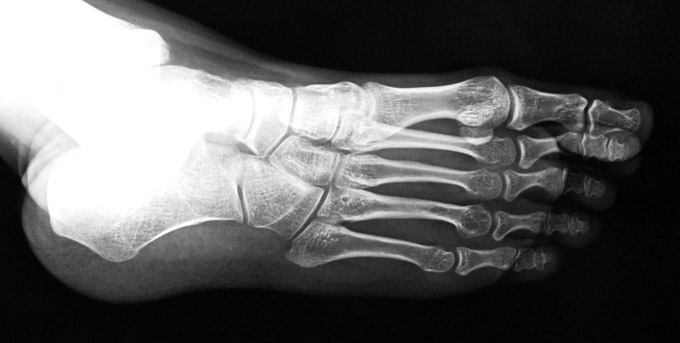

El parmağı (metakarp) ve ayak parmağı (metatars) kısalıkları doğuştan tek başına, geniş bir sendrom grubuyla birlikte, travma sonrası, Freiberg hastalığı (avasküler nekroz) sonrası görülebilir.

Doğuştan metakarp ve metatars kısalığının görülme sıklığı 1/1000’den azdır. Kadınlarda erkeklere göre 5 kat daha fazla görülür ve sıklıkla (%72) iki taraflıdır. En sık 4. parmak tutulur. Bu tür olgularda sorunun nedeni tam olarak bilinmemekle brlikte deformitenin genellikle epifiz plağının erken kapanmasından kaynaklandığı düşünülmektedir.

Metakarp kısalığında kozmetik görünümün bozulması ve dominant elin kullanımı sırasında yorulma, metatars kısalığında ise kozmetik haricinde metatarsalji, kısa parmağın dorsale kayması sonucu deformite oluşması, plantar yönde açılanması sonucu ağrı ve bası ülserleri, ve ayakkabı giymede zorluk nedeniyle ameliyat gerekebilir.